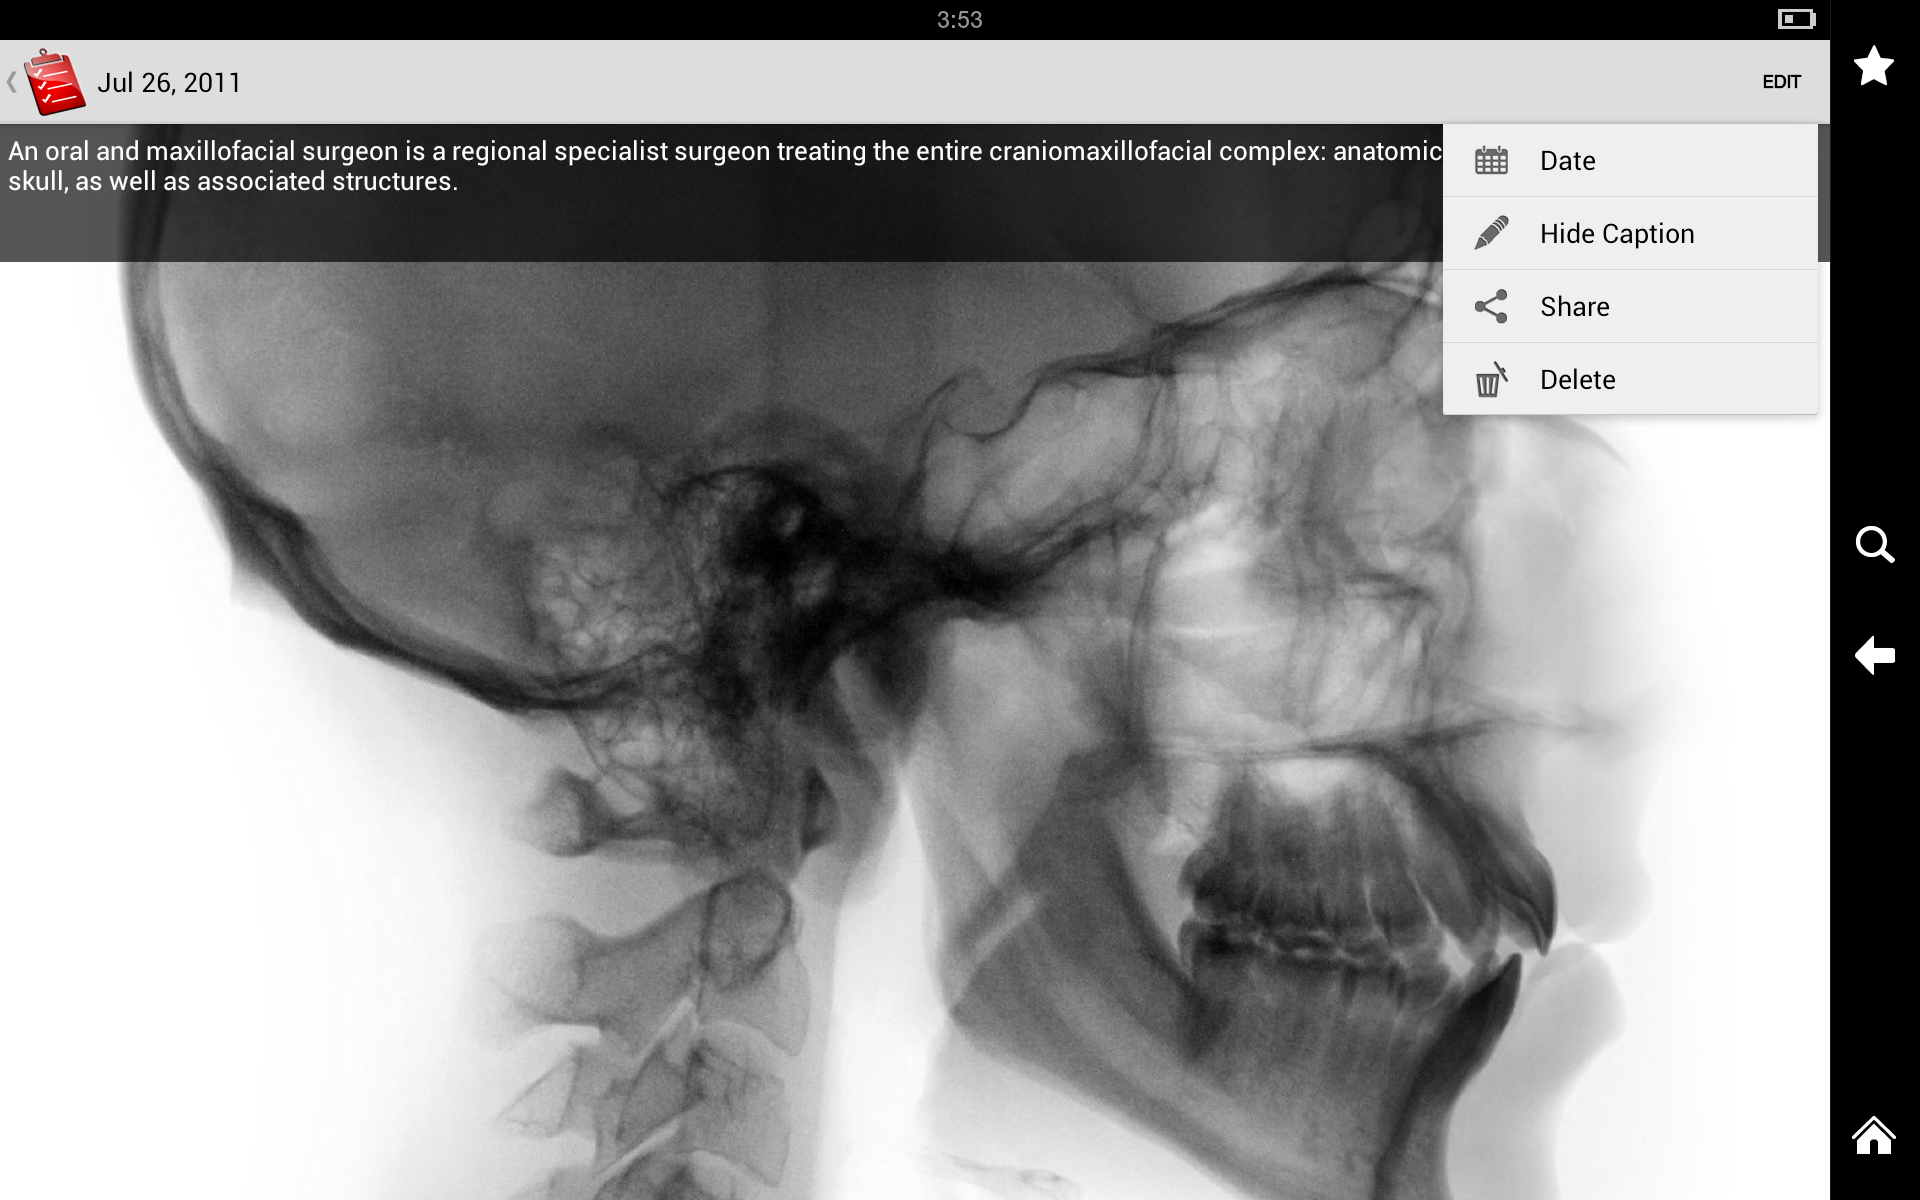

Test Results

My Medical allows you to store and track the results of medical tests such as blood work, x-rays, and MRIs. You can also add notes to provide context for the results.

My Medical allows you to store and track the results of medical tests such as blood work, x-rays, and MRIs. You can also add notes to provide context for the results.

User Interface

My Medical has a clean, intuitive interface that makes it easy to navigate and use. The app is organized into tabs for each section, making it easy to find the information you’re looking for. The buttons and menus are clearly labeled, and the app uses intuitive icons to represent different functions.